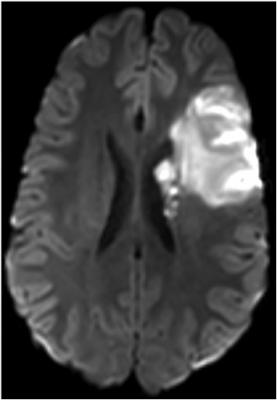

Preliminary results from the partnership’s first study, the “Value of Advanced Imaging in Improving Health Outcomes and Healthcare Spending in Acute Stroke1,” indicate that advanced imaging is preferred in acute stroke care leading to improved long-term health outcomes. The principal investigator, Pina Sanelli, M.D., vice chair for research at Northwell Health, noted that the optimal choice of computed tomography (CT) or magnetic resonance imaging (MRI) varies by patient’s specific characteristics, promoting a patient-centered imaging approach in which each patient will receive the imaging exam that will result in best outcomes based on their own personal features. These early findings suggest that further investigation is needed to perform a more-comprehensive analysis of the long-term benefits, harms and costs for different imaging approaches in acute stroke care incorporating a variety of personal characteristics.